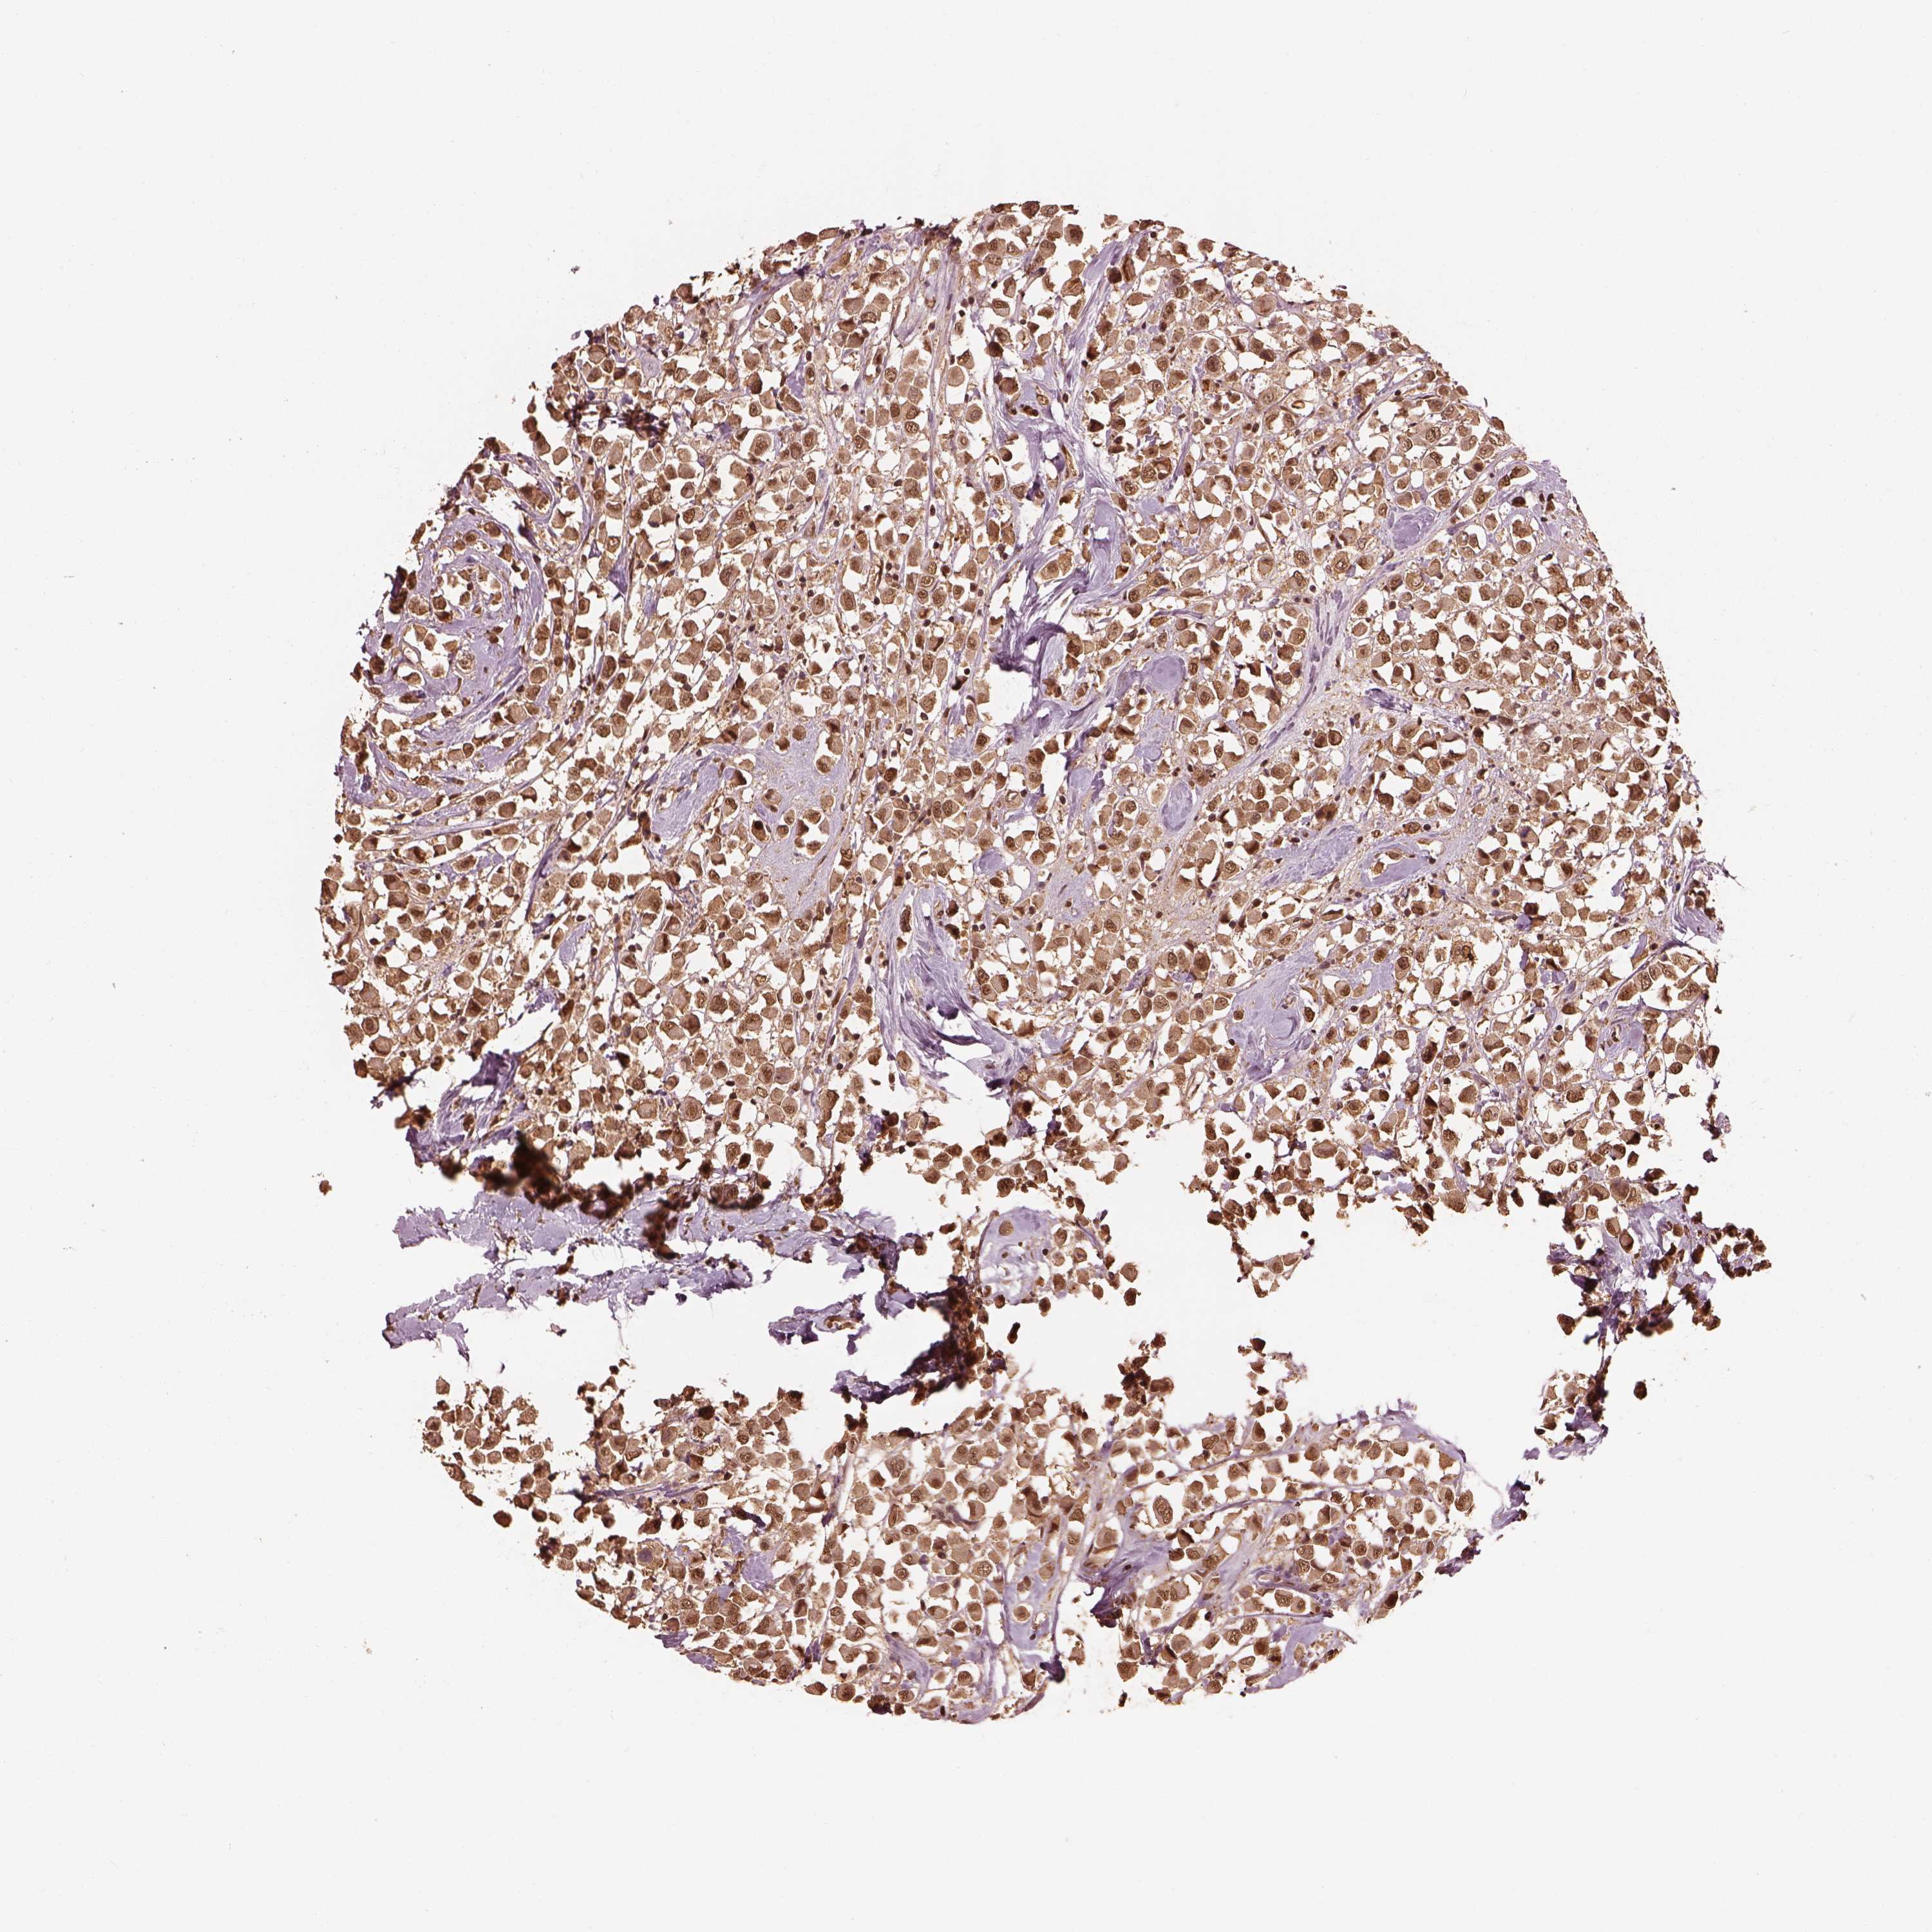

CANCER BREAST CANCER Show tissue menu

BRCA TCGA BRCA VALIDATION PROTEIN EXPRESSION